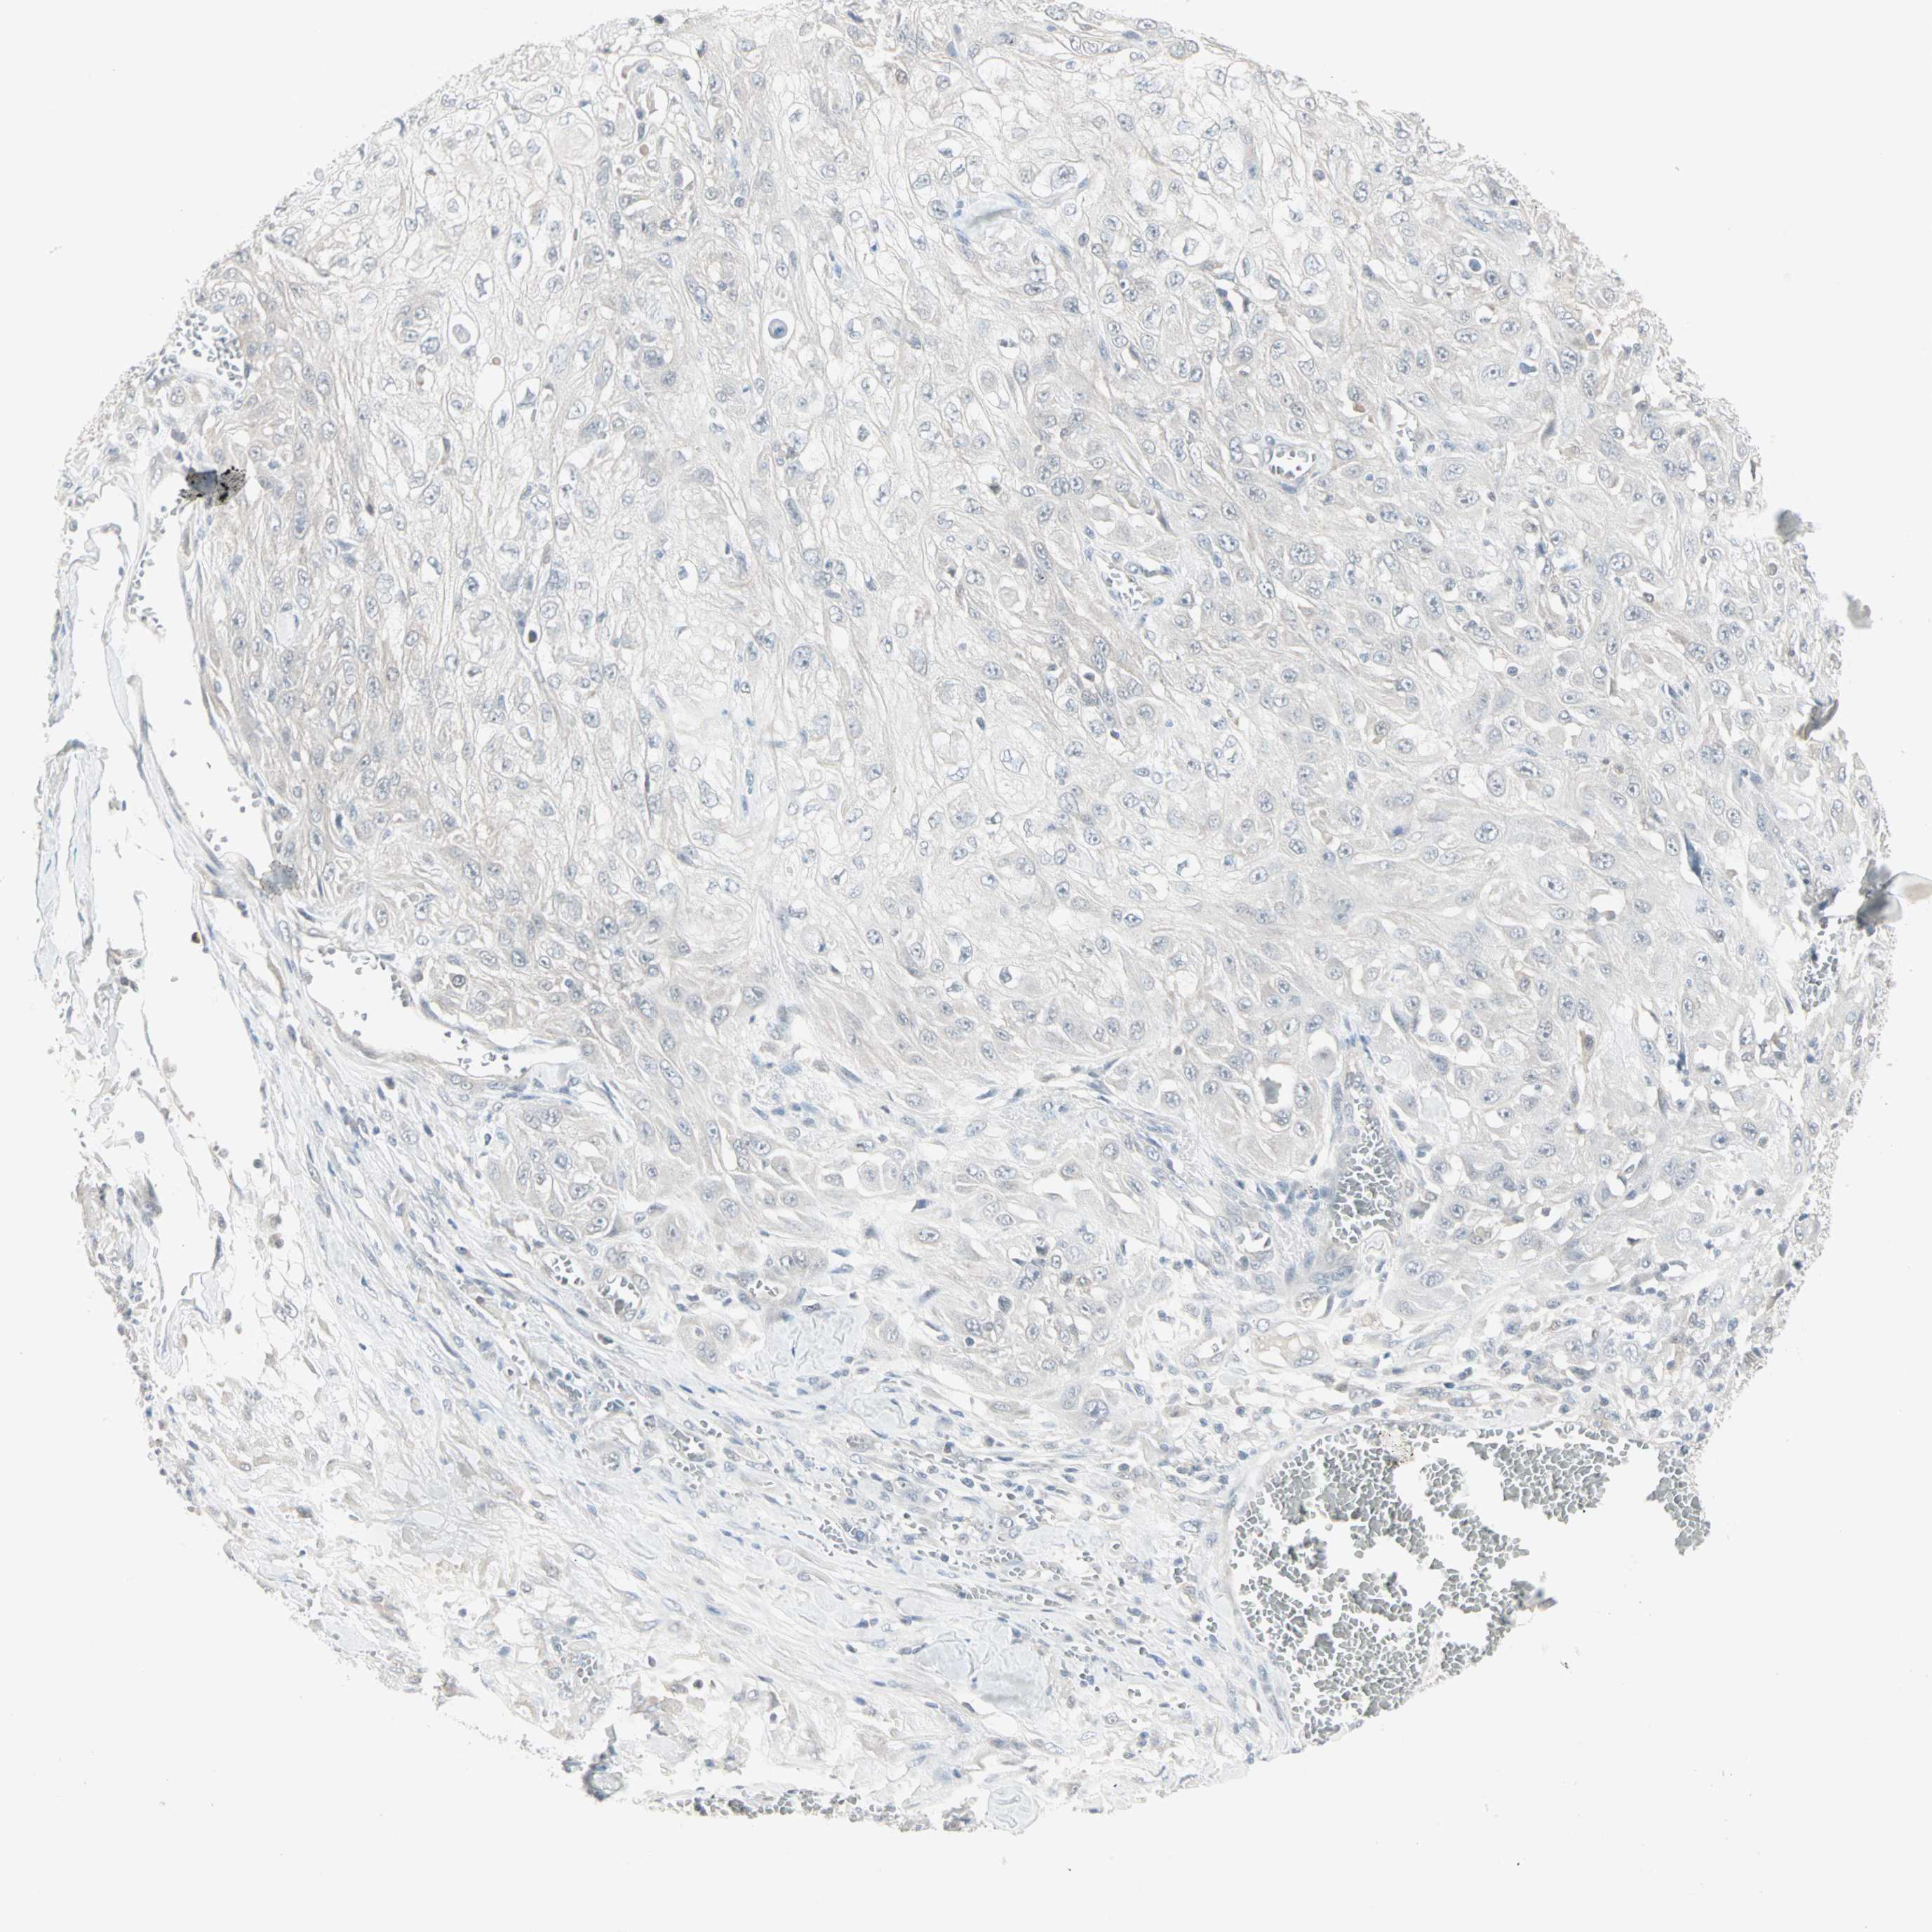

SKIN CANCER - Protein expressioni

A mouse-over function shows sample information and annotation data. Click on an image to view it in a full screen mode. Samples can be filtered based on level of antibody staining by selecting one or several of the following categories: high, medium, low and not detected. The assay and annotation is described here.

Antibody stainingi

Antibody staining in the annotated cell types in the current human tissue is reported as not detected, low, medium, or high, based on conventional immunohistochemistry profiling in selected tissues. This score is based on the combination of the staining intensity and fraction of stained cells.

Each image is clickable and will lead to virtual microscopy that enables deeper exploration of all samples and also displays staining intensity scores, fraction scores and subcellular localization as well as patient and tissue information for each sample.

CAB035999

Staining

High

Medium

Low

Not detected

Intensity

Strong

Moderate

Weak

Negative

Quantity

>75%

75%-25%

<25%

None

Location

Nuclear

Cytoplasmic/membranous

Cytoplasmic/membranous,nuclear

Squamous cell carcinoma, metastatic, NOS